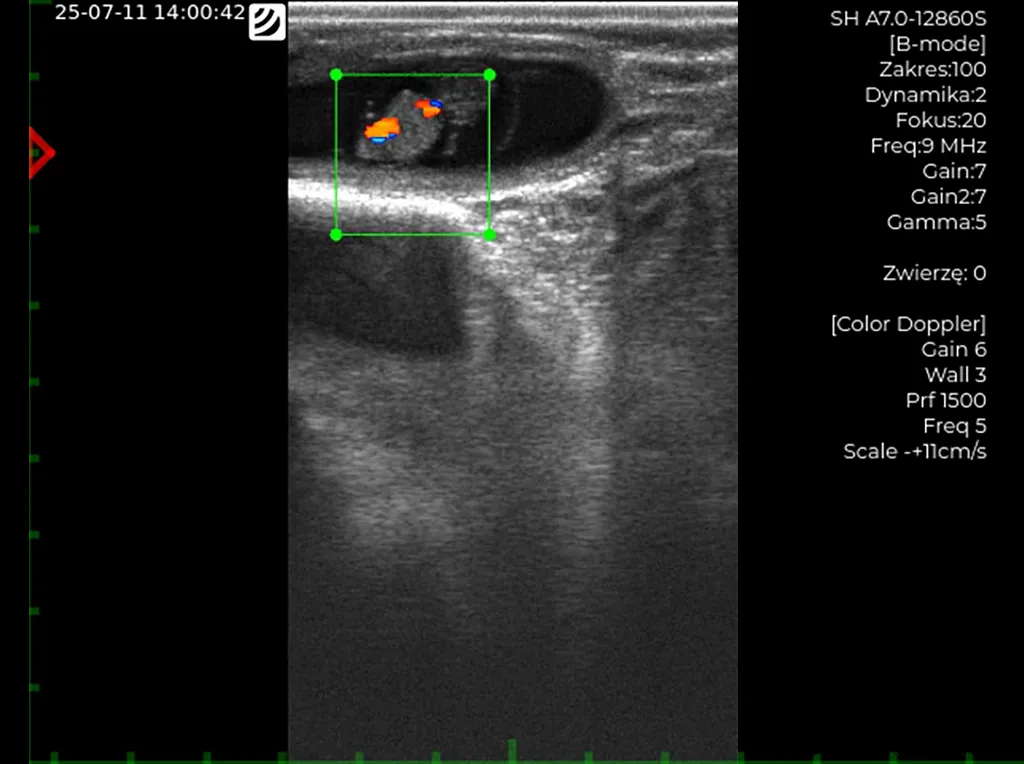

Examen Doppler (ecógrafo iScan 3) – latido cardíaco fetal visible.

• Examen ecográfico de gestación temprana para evaluar el desarrollo de la gestación y la viabilidad del embrión